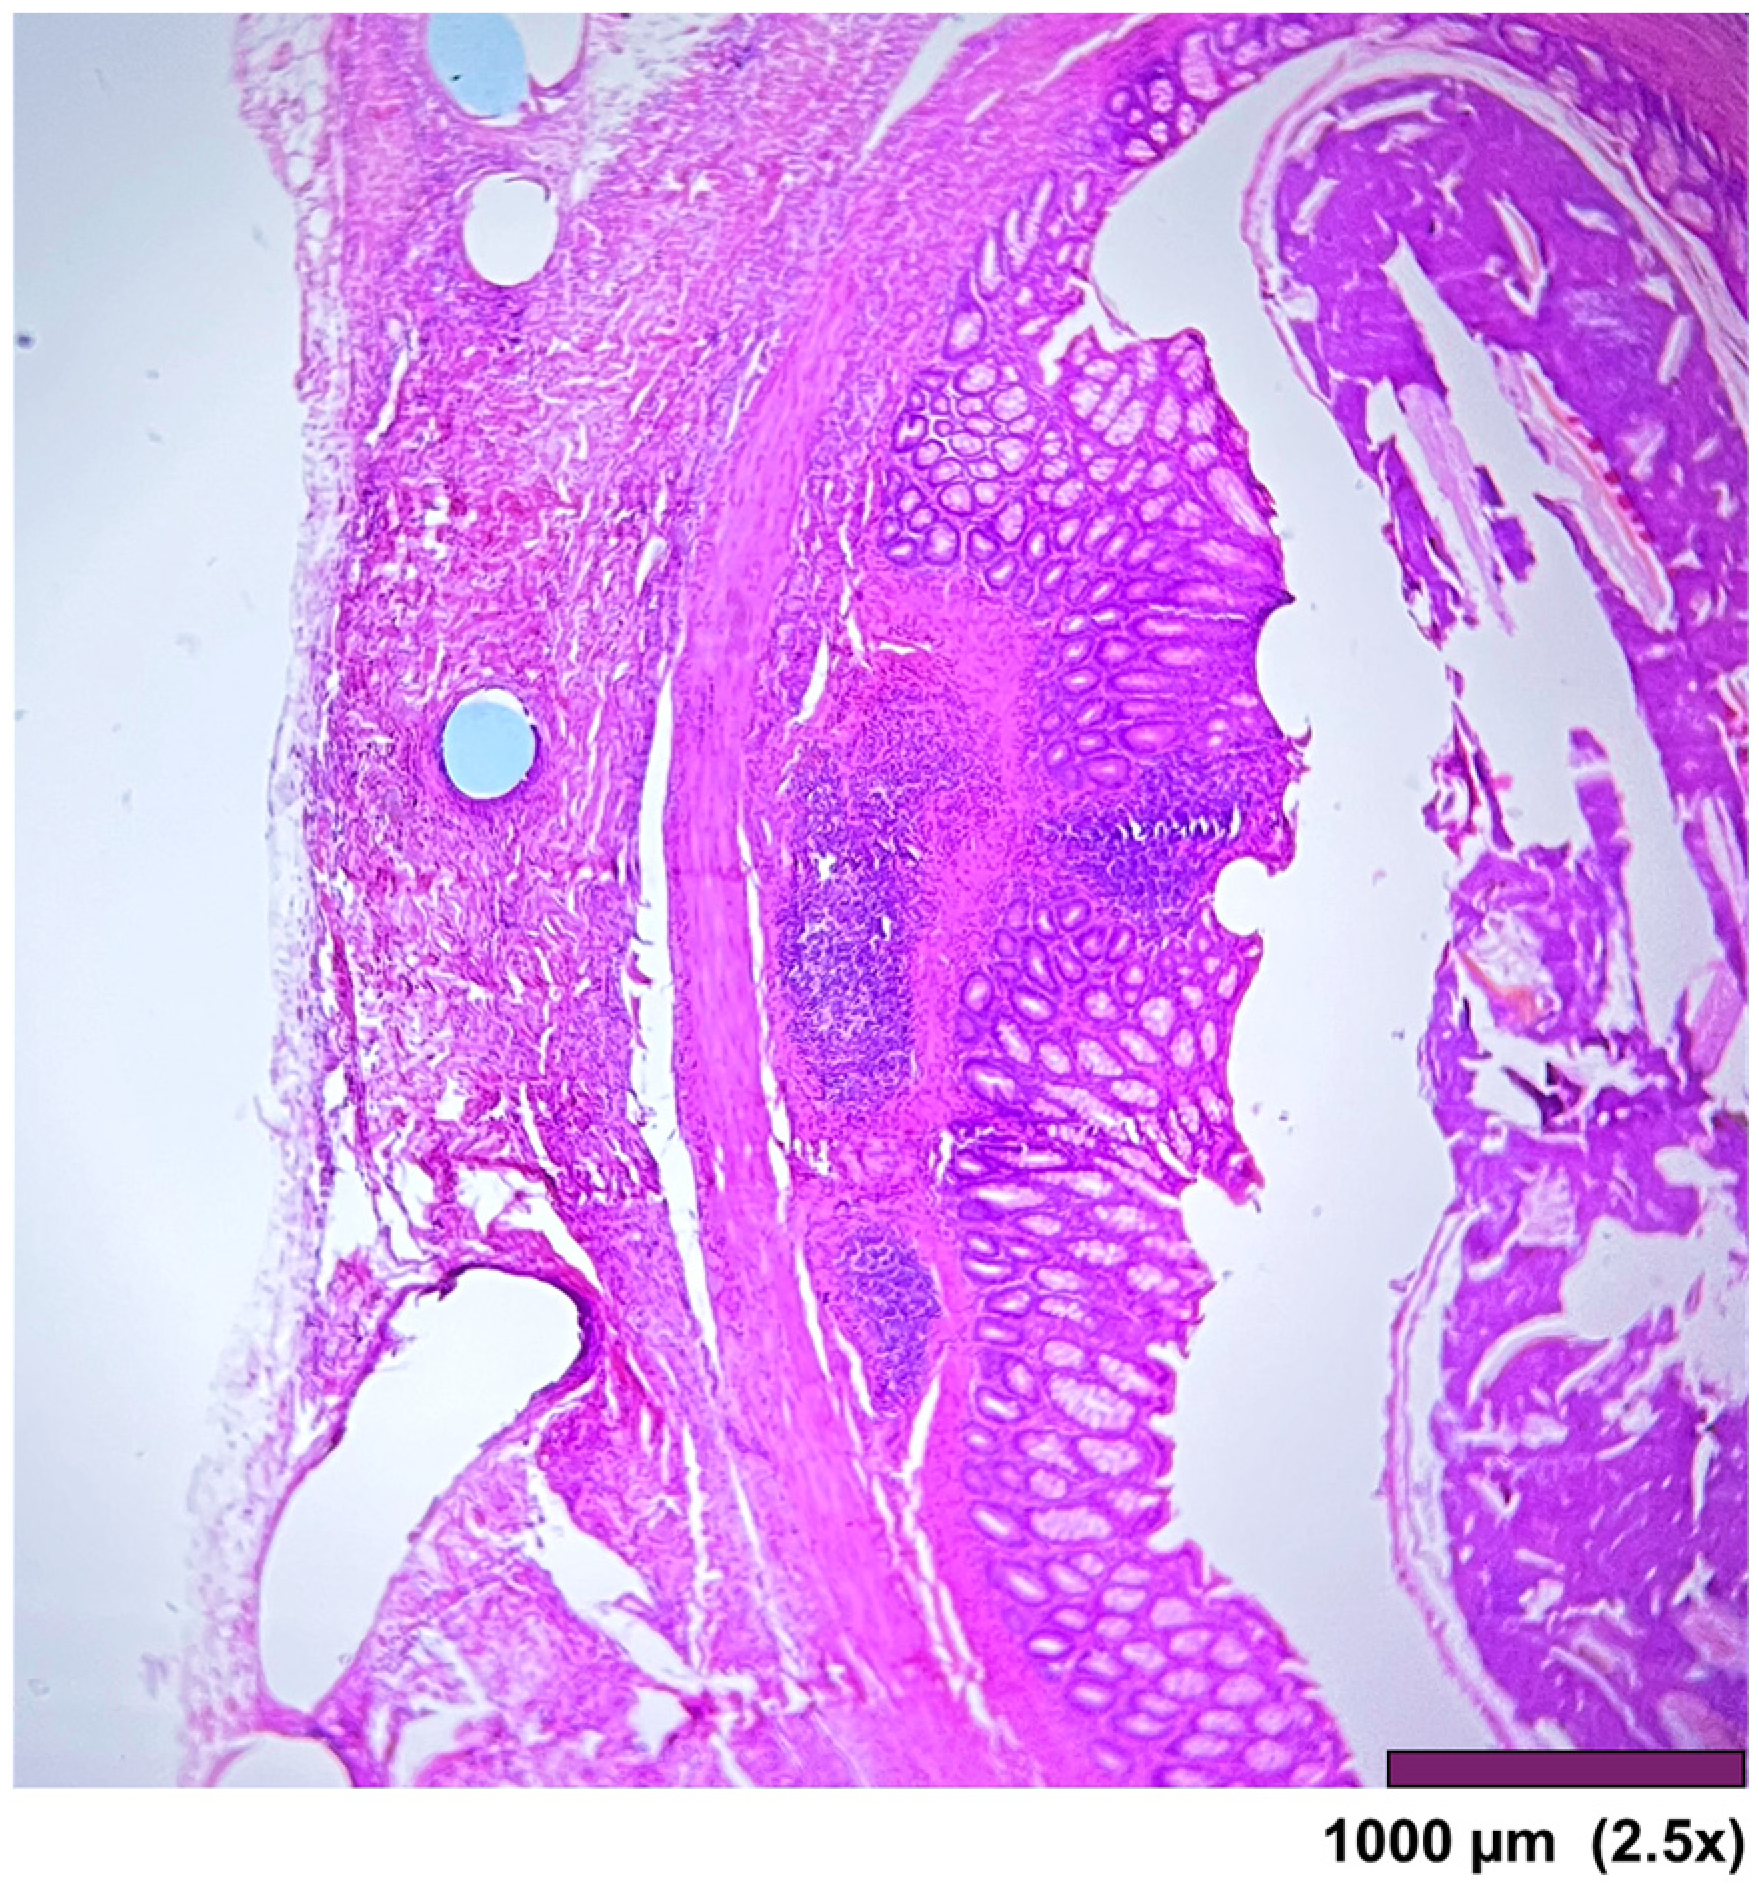

The stomach wall showed (Figure 5) minimal architectural difference between the native and the regenerated stomach fragment, with mild fibrosis and moderate infiltration of inflammatory cells in the subserosal layer. In one sample, the SIS-covered stomach portion of the muscularis propria was replaced by a thick layer of fibrosis (Figure 6).

Figure 5. All layers in the stomach wall-mucosa, submucosa, muscularis propria, and serosa. There is a minimal architectural difference between the native and the regenerated stomach, with mild fibrosis and moderate infiltration of inflammatory cells in the subserosal layer. (2.5×, HE).